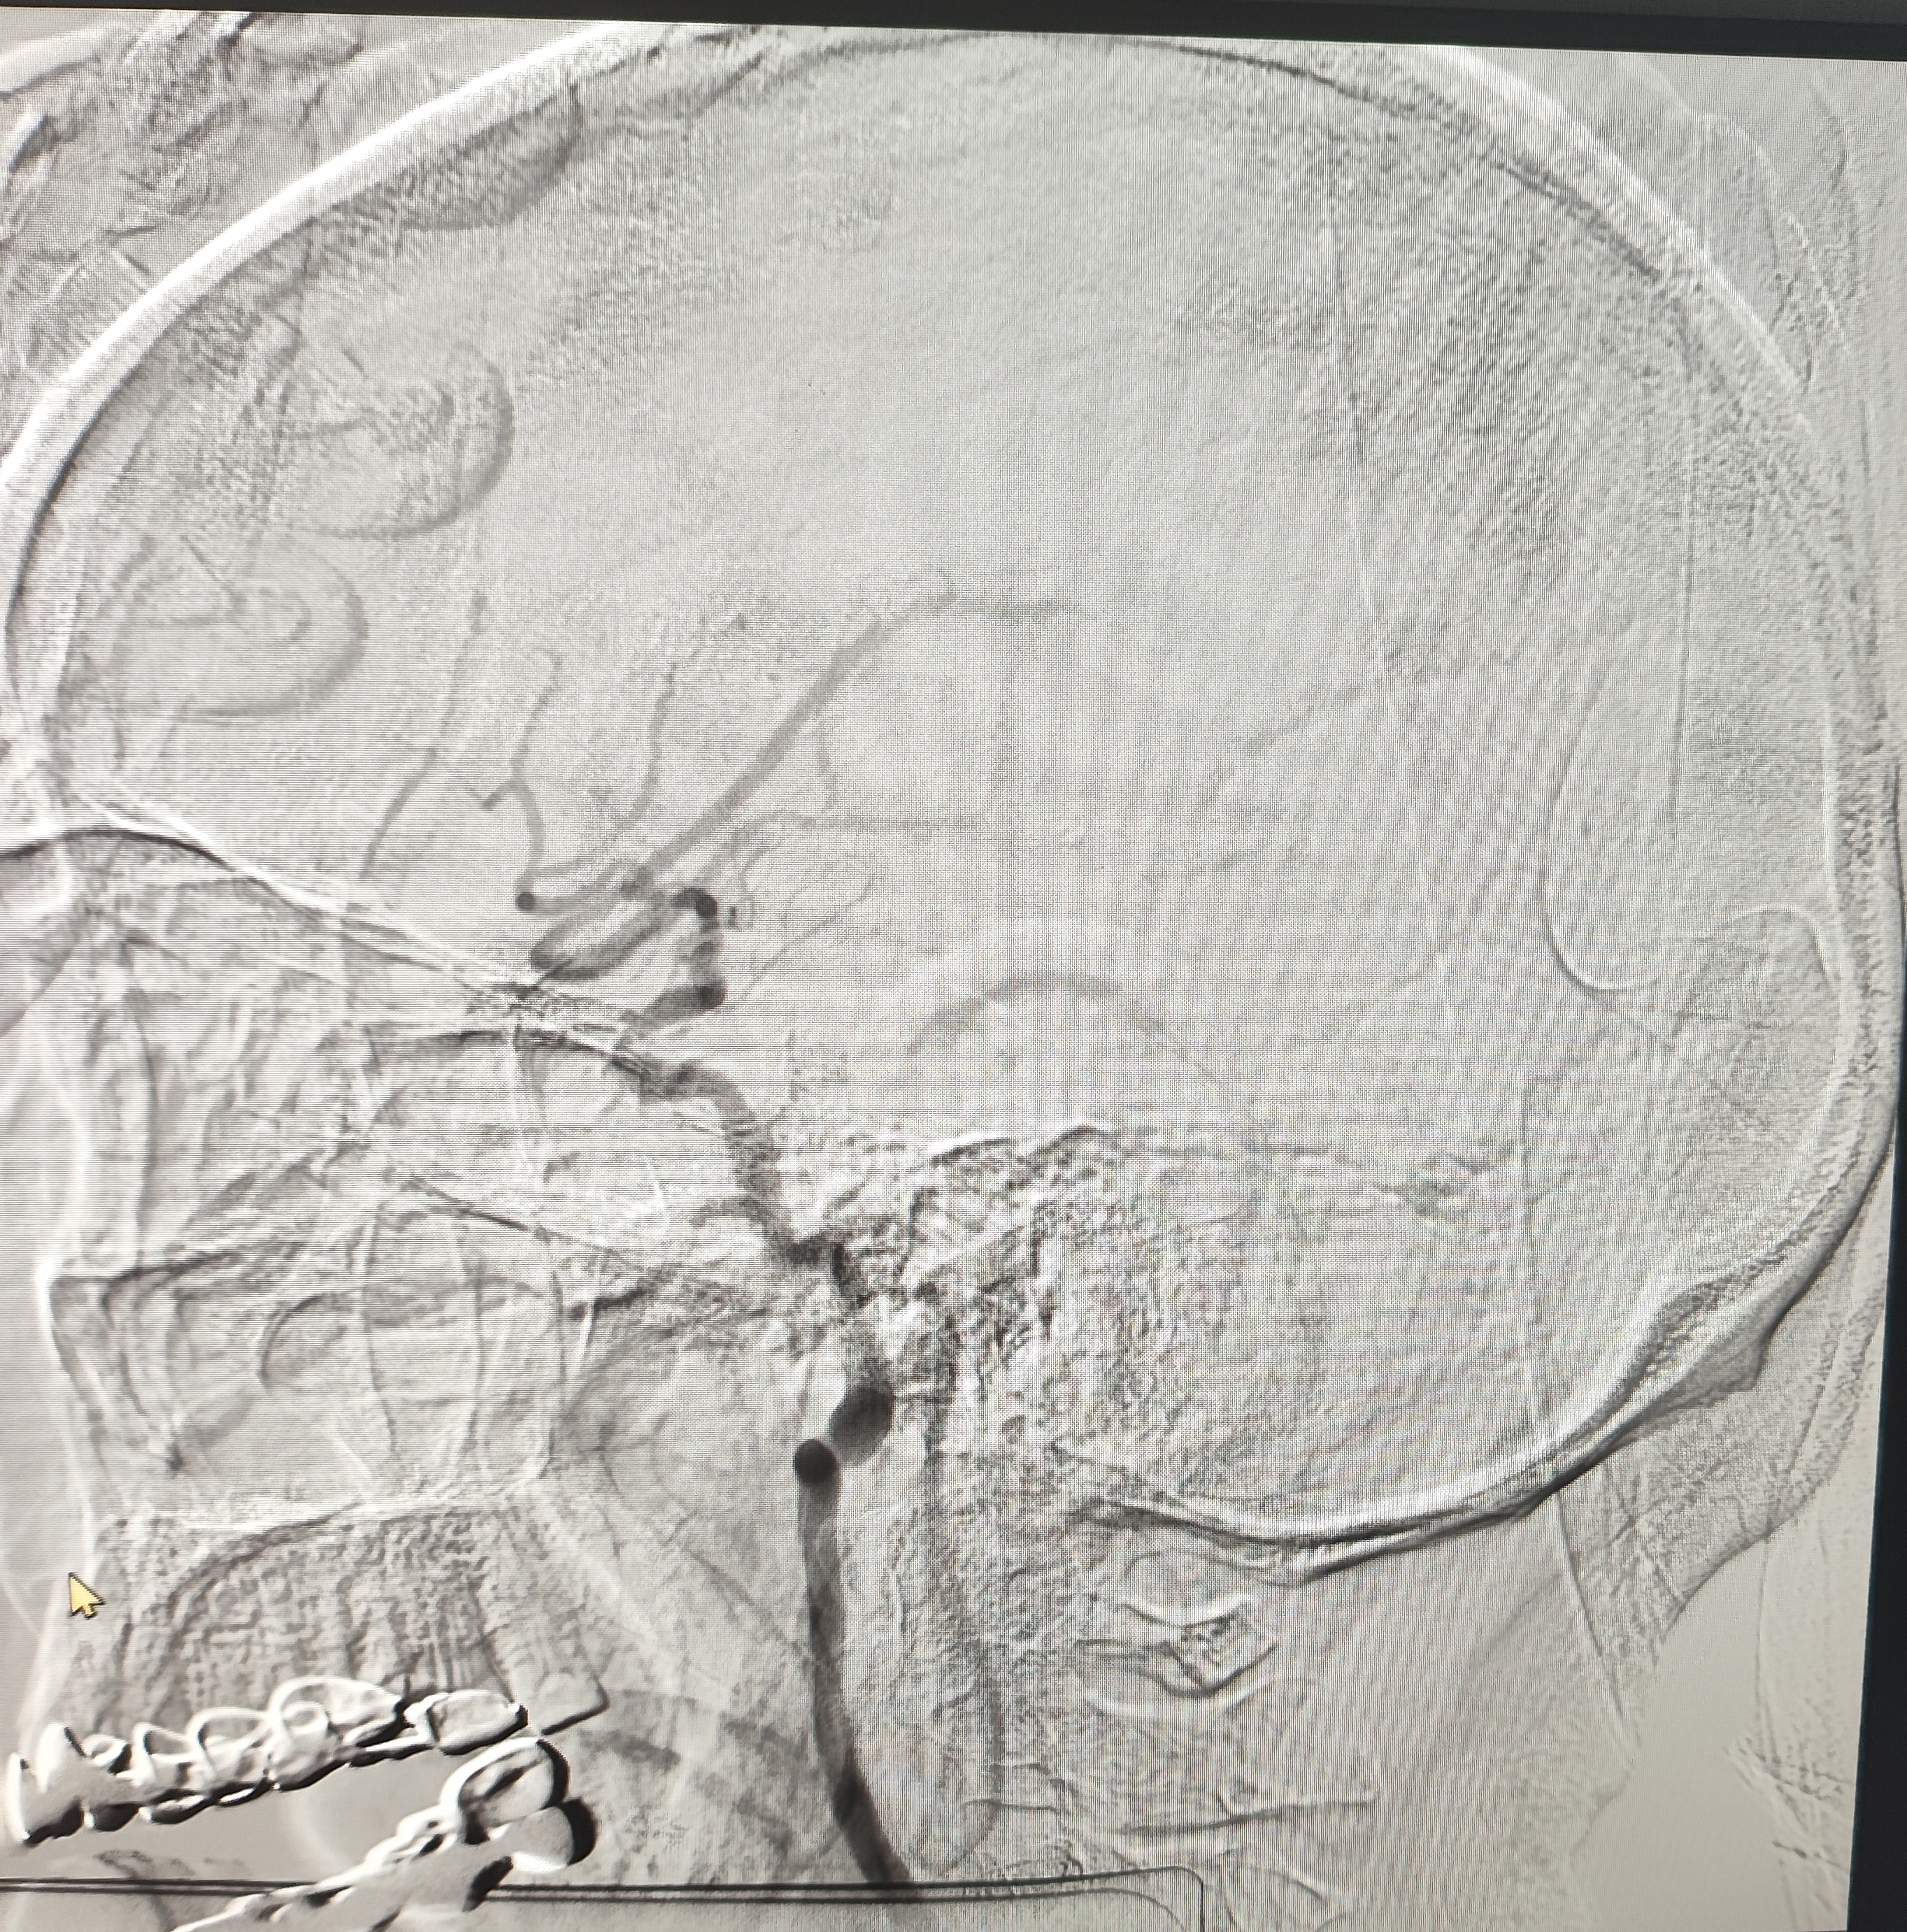

颈总巨大斑块急性闭塞的血管内治疗(双颈动脉支架桥接+支架释放后掉斑块,抽吸取栓)

84岁男性,既往右侧颈动脉狭窄病史8个月,多次脑梗未治疗,本次突发左侧肢体无力来诊,发病30小时后转入我院。

症状进行性加重,意识逐渐模糊,烦躁,左上肢肌力1级,左下肢肌力2级,当地考虑开通难度大,转入我院。

急诊上台。